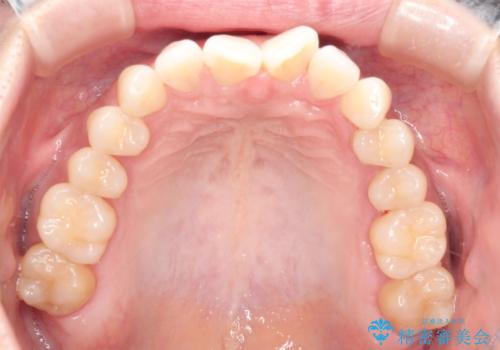

前歯のがたつきと隙間の矯正 インビザラインにて

- 上顎の前歯のがたつきと、下の前歯の隙間を主訴に来院されました。

下の前歯が先天的に欠損していました。

上顎の歯と歯の間をわずかに削りスペースを作り、ガタガタの改善し、下顎の前歯は隙間を閉じる計画としました。

非常に協力的な患者様でしたので、早期に治療が終了することができました。